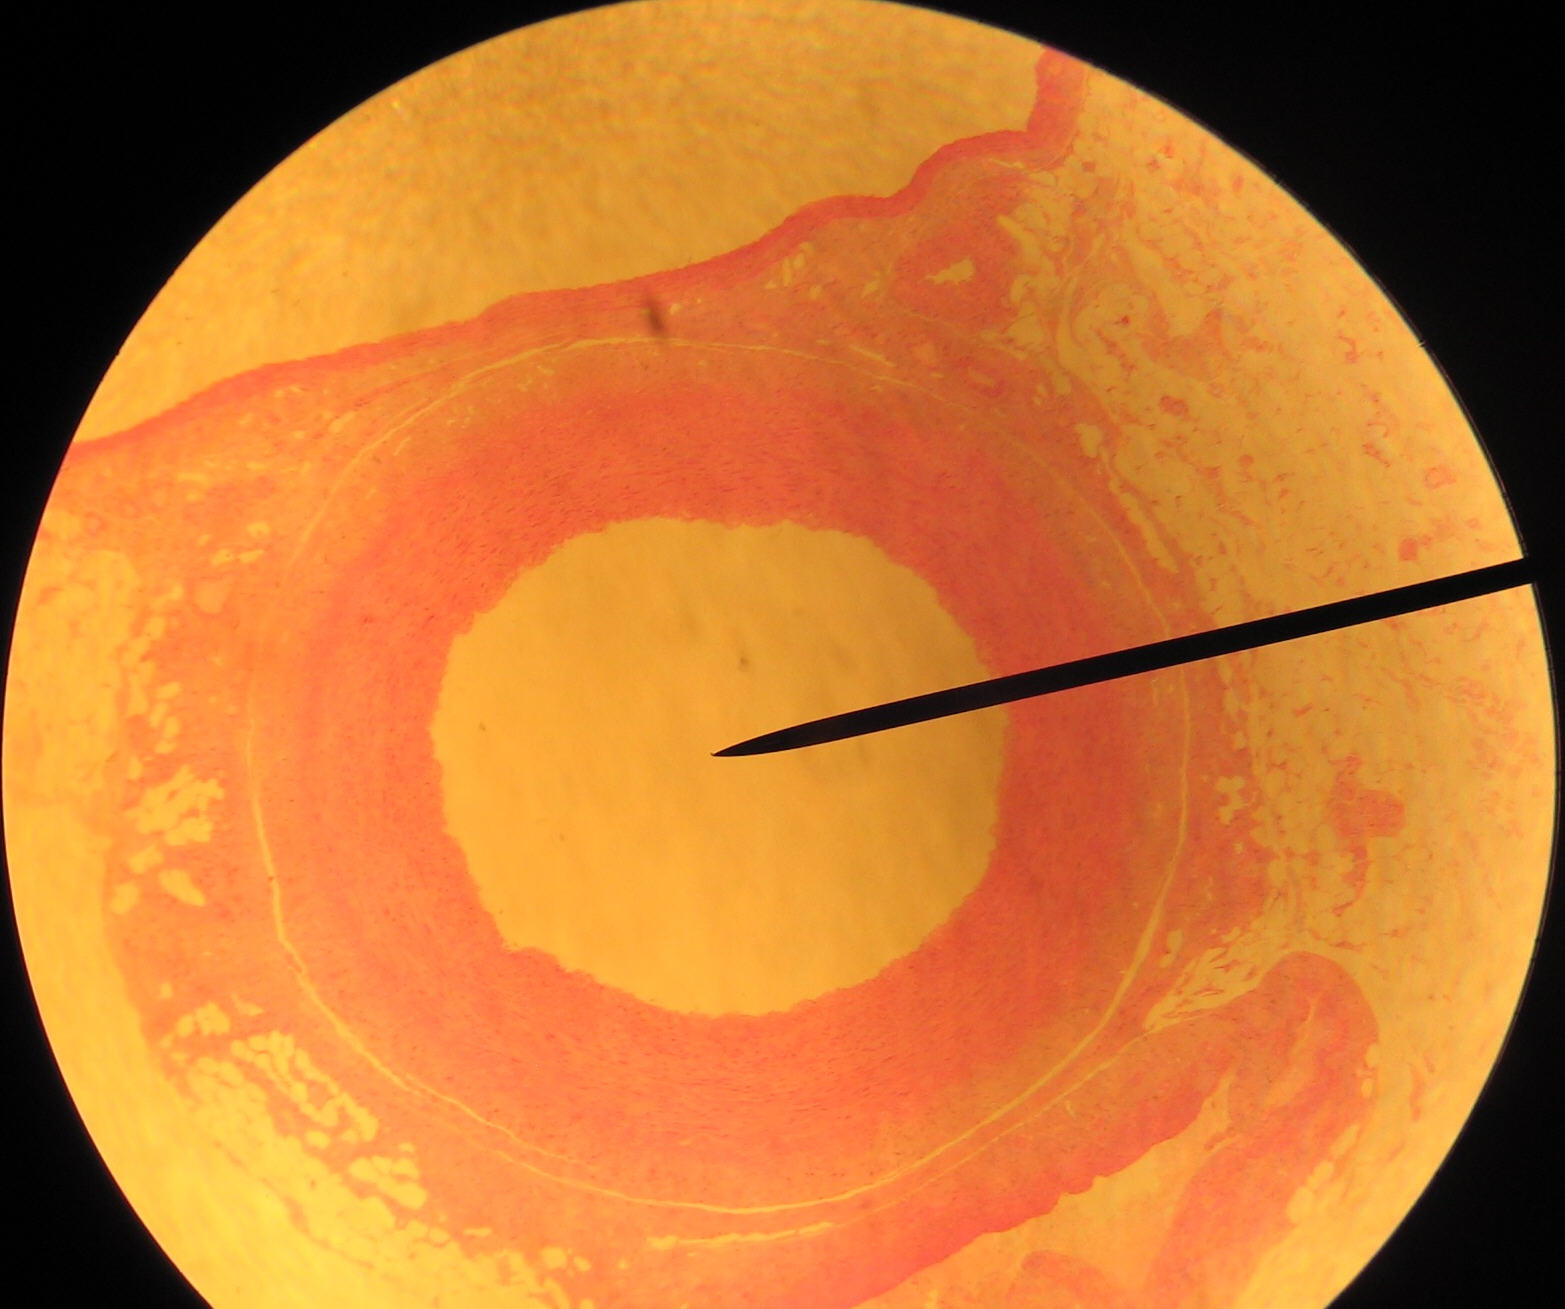

Artery Slide